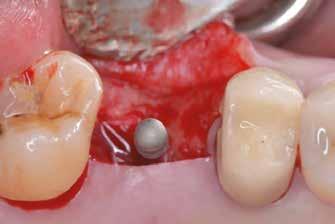

Az eljárást helyi érzéstelenítés mellett végeztük (4%-os articaine-hidroklorid 1:100 000 adrenalinnal). Papillakímélő, U alakú palatális bemetszést végeztünk, teljes vastagságú nyálkahártyalebeny preparálás történt, a lebenyt bukkálisan feltekertük (5. ábra). A lebeny bukkálisan feltekert részén de-epitelizációt végeztük el, amellyel kompenzálni tudtuk a bukkális lágyszöveti defektust. Szakaszos előfúrást végeztünk, és a bredent copaSKY 4x10 implantátumot 30 Ncm behajtási nyomatékkal helyeztük be (6. ábra). Az implantátumot 1 mm-re szubkresztálisan helyeztük be, hogy később szélesebb emergenciaprofilt tudjunk kialakítani (7. ábra). Az egyedi ínyformázó úgy készült, hogy kompozitot vittünk fel a titánbázisra, és így formáztuk a lágyszöveteket a transzgingivális gyógyulási fázis során (8. ábra). Az egyéni ínyformázó tulipán formájú, hogy kialakítsa a kívánt emergenciaprofilt. A lágyszövetet feszülésmentesen zártuk #6/0 nem felszívódó, monofil fonallal (Optilene, B. Braun Deutschland; 9. a–b. ábra). Posztoperatív röntgenfelvétel készült, ami alapján az implantátum a szomszédos fogakkal párhuzamos elhelyezést mutatott (10. ábra). Posztoperatív utasításokat adtunk a páciensnek a műtéti terület körüli szájhigiénia fenntartása érdekében. A beavatkozást követő egy héttel a varratokat eltávolítottuk, és a kezelt terület kielégítő gyógyulást mutatott (11. ábra). A 4 hónap utáni késleltetett terhelést a páciens kívánsága szerint terveztük.

1. ábra: Műtét előtti fogászati panorámafelvétel, amelyen a hiányzó felső állcsont jobb első premolárisát és a szabad véggel rendelkező hidat láthatjuk. — 2. ábra: Az implantátum méreteinek megtervezése CBCT-vel. 3. ábra: Bukkális lágyrészdefektus. — 4. ábra: A biológiai szélesség értékelése a vertikális lágyszövetvastagság alapján. 5. ábra: Palatinális „tekercslebeny” – Palatal roll flap. — 6. ábra: Bredent medical copaSKY 4x10 implantátumbeültetés. 7. ábra: Szubkresztális implantátumbeültetés a várható biológiai szélességnek megfelelően.

8. ábra: Egyéni ínyformázó titánbázison, tulipán alakú emergenciaprofillal. — 9. a. ábra: A sebzárás okkluzális nézete.

(2. ábra). A lágyszövetek értékelése Seibert szerinti I. osztályú csontdefektust állapított meg (3. ábra), ezért a beavatkozáskor palatinális „tekercslebenyt” preparáltunk (palatal roll flap), és implantációt végeztünk, hogy kompenzálni tudjuk a bukkális lágyszövet-behúzódást. Megmértük a vertikális lágyszövetvastagságot, és úgy terveztük, hogy a szubkresztális implantátum beültetése összhangban legyen a biológiai szélesség kialakulásával a transzgingivális gyógyulási periódus alatt (4. ábra)